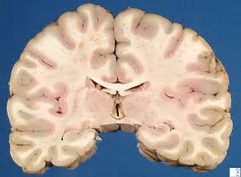

মানুষের মস্তিষ্কের গঠন কমবেশি একই, প্রায় ৪০ ভাগ গ্রে ম্যাটার আর ৮০ ভাগ হোয়াইট ম্যাটার। কিন্তু তারপরও ছেলেদের সাথে মেয়েদের মস্তিষ্কের কিছু গঠনগত পার্থক্য রয়েছে যার কারণে ছেলেদের তুলনায় মেয়েরা কথা বেশি বলে আবার মানচিত্র ছেলেরা ভালো ও দ্রুত বুঝতে পারে। কিন্তু কেন এমন হয়? বিভিন্ন গবেষণার মাধ্যমে এর উত্তর পাওয়া গিয়েছে।

ইন্টেলিজেন্স টেস্ট এর মাধ্যমে দেখা যায় ছেলেরা মেয়েদের তুলনায় ৭ গুণ গ্রে ম্যাটার ব্যবহার করে আবার মেয়েরা ৯ গুণ বেশি হোয়াইট ম্যাটার ব্যবহার করে। গ্রে ম্যাটার এর অন্যতম কাজ হল লজিক্যাল বিষয় যেমন অবস্থান সম্পর্কে ধারণা, মানচিত্র পঠন, গণিত, ও প্রব্লেম-সলভিং জাতীয় কাজগুলো করা। অন্যদিকে হোয়াইট ম্যাটার মস্তিষ্কের প্রসেসিং সেন্টারগুলোকে যুক্ত করে, যা ভাষাগত দক্ষতা, ইমোশনাল চিন্তা ও একসাথে অনেক কাজ করতে ভূমিকা পালন করে।

যেহেতু মেয়েদের হোয়াইট ম্যাটার বেশি ব্যবহৃত হয়, তাই তারা ভাষাগত যোগাযোগে বেশি পারদর্শি। প্রকৃতপক্ষে, ছেলেদের তুলনায় মেয়েদের মস্তিষ্কের অনেক বেশি অংশ এই যোগাযোগের কাজে ব্যবহৃত হয় ফলে তারা ভাষাকে সামাজিক বন্ধন গঠনের হাতিয়ার হিসেবে ব্যবহারে অধিক পারদর্শি, আর ছেলেরা ভাষা ব্যবহার করে তথ্য আদানপ্রদান ও সমস্যা সমাধানের মাধ্যম হিসেবে। গড়ে, একজন মহিলা দিনে ৭০০০ শব্দ আর পুরুষ দিনে ২০০০ শব্দ ব্যবহার করে।

ছেলেদের তুলনায় মেয়েদের মস্তিষ্কের দুটি অংশের (হেমিস্ফেয়ার) মধ্যে যোগাযোগ আরও বেশি কার্য্যকর, তাই ছেলেরা যখন একসময়ে একটি কাজেই মনোনিবেশ করে, তখন মেয়েরা একাধিক কাজ করতে পারে। ধারণা করা হয়, এই অধিক কার্য্যকরী যোগাযোগের জন্যই মেয়েদের স্বভাবসুলভ বৈশিষ্ট্য প্রকাশ পায়।এই পার্থক্যগুলো প্রাগৈতিহাসিক সময় থেকেই ধীরে ধীরে গড়ে উঠেছে। যখন পুরুষেরা শিকারের খোঁজে বের হত এবং তাদের শিকারের অবস্থান নির্ণয় ও সমস্যা সমাধানে মস্তিষ্ক বেশি ব্যবহৃত হত, আর নিজেদের ঘরবাড়ি ও সন্তানদের নিরাপত্তা ও বেড়ে ওঠা নিশ্চিত করতে মহিলাদের ভাষাগত দক্ষতা অর্জন করতে হয়েছিলো।